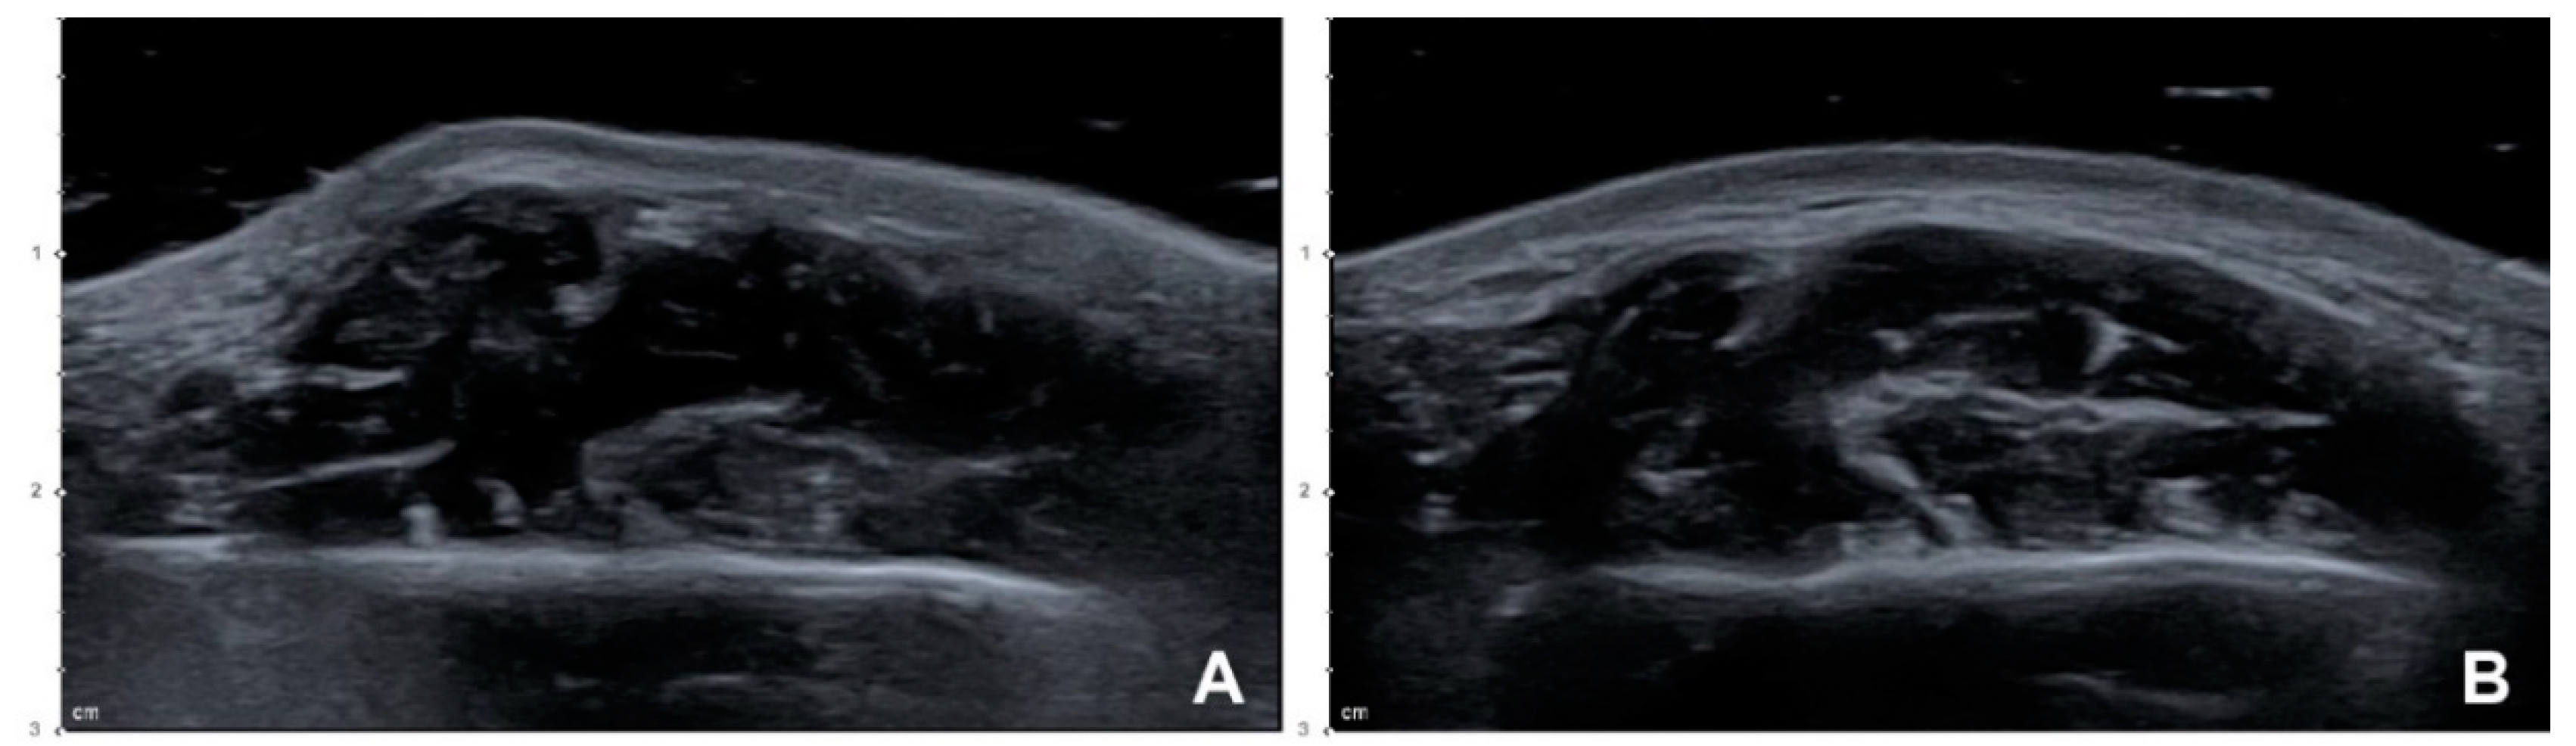

Figure 3.

US images showing reduction of the masseter after BoNT-A injections (B mode, transverse view, 15-MHz linear transducer): (A) Left side, before the injection, (B) left side, 1 month after a conventional blind injection, (C) right side, before the injection, and (D) right side, 1 month after a US-guided injection.

The thicknesses of the masseters on the left and right sides were 12.33 ± 2.92 mm (mean ± SD) and 13.00 ± 3.26 mm, respectively, before the injection, and 10.74 ± 2.77 mm and 10.81 ± 2.91 mm 1 month after the injection. The reduction in the thickness of the masseter in the resting state differed significantly at 1 month after the injection between the conventional blind injection group and the US-guided injection group (Figure 3) by 12.38 ± 7.59% and 17.98 ± 9.65%, respectively (t(19) = 3.059, p = 0.007) (Table 1).